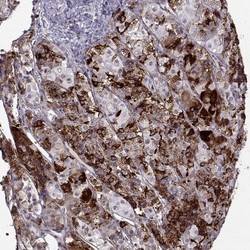

- Immunohistochemistry-Paraffin: VGF Antibody [NBP2-31596] - Staining of human pituitary gland shows strong cytoplasmic positivity in anterior cells.